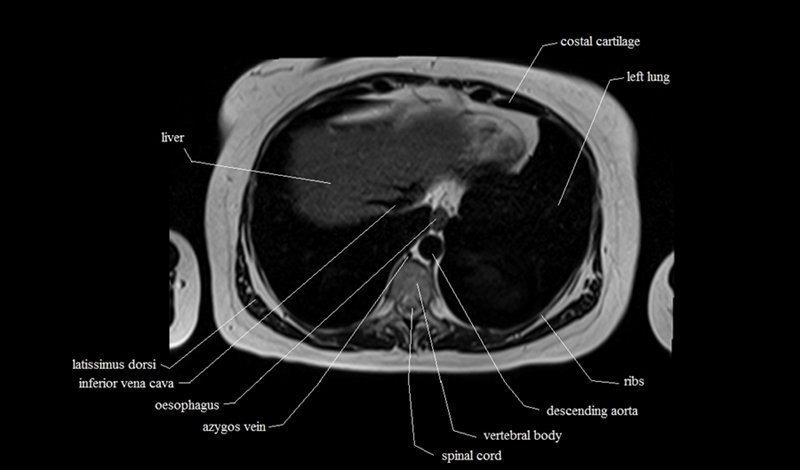

MRI Axial Cross Sectional Anatomy of Chest

This MRI chest (thorax) axial cross sectional anatomy tool is absolutely free to use. Use the mouse scroll wheel to move the images up and down, or alternatively, use the tiny arrows (→) on both sides of the image to navigate through the images. For a more detailed view, double-click the image to view it in full screen, and use the menu in the top right-hand corner to view individual slides or play them in a loop.